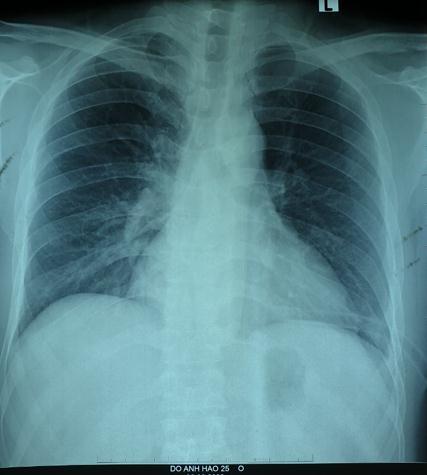

Tại đây, bệnh nhân H. đã được chỉ định mổ nội soi để sửa tổn thương và phục hồi cơ hoành. Khi đưa máy soi vào ổ bụng, phẫu thuật viên nhận thấy gần toàn bộ đại tràng ngang, lách, dạ dày và mạc nối lớn đã chui qua cơ hoành lên khoang màng phổi bên trái. Sau khi đưa các tạng trên trở lại ổ bụng, tổn thương cơ hoành bên trái lộ rõ là một lỗ khuyết rộng khoảng 6×8 cm. Đây chính là nguyên nhân gây ra thoát vị, kết hợp với tiền sử có chấn thương, chẩn đoán trong mổ là thoát vị hoành trái do vỡ cơ hoành. Cơ hoành vỡ đã được các phẫu thuật viên khâu phục hồi kín, ca mổ diễn ra trong 1 giờ 30 phút. Sau mổ, bệnh nhân ổn định, hết đau ngực, khó thở, chụp phim X.quang kiểm tra thấy phổi nở tốt, không còn hình ảnh thoát vị. Bệnh nhân H. được ra viện sau 6 ngày với sẹo mổ rất nhỏ của phẫu thuật nội soi.

Ảnh 5: X.quang ngực thẳng sau phẫu thuật: Không thấy hình ảnh thoát vị hoành